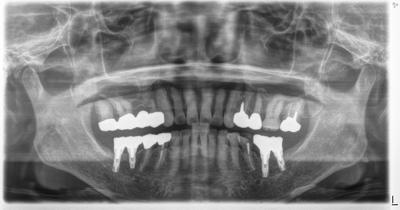

HOME > ブログ 一覧 > インプラント包括ケース 2020.12.24インプラント包括ケース 様々な分野を駆使した包括診療、術後10年以上、問題なし。 Recent Entries アライナー矯正(インビザライン、シュアスマイル)費用を2023年 1月から改訂させていただきます(01/09) 本年もよろしくお願いいたします(01/02) 年始の診療について(01/01) 新しいWEBへ移行、年末年始の診療のお知らせ(12/29) ダラダラ根管治療行っても治らないという事(12/21) Category その他の治療(126) インビザライン・矯正(52) インプラント治療(216) ホワイトニング(47) メインテナンス(21) 包括診療(95) 医院からのお知らせ(249) 審美治療(128) 日々雑感(283) 根管治療(100) 歯周病治療(90) 矯正(73) 補綴治療(45) 補綴治療カテゴリを追加(1) 診療全般(44) Archive 2023年1月(3) 2022年12月(6) 2022年11月(14) 2022年10月(6) 2022年9月(8) 2022年8月(7) 2022年7月(13) 2022年6月(8) 2022年5月(7) 2022年4月(7) 2022年3月(6) 2022年2月(7)